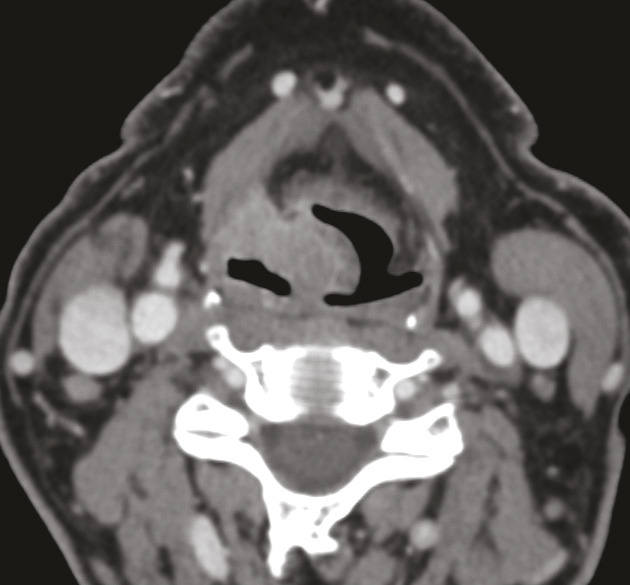

La délimitation entre l’oropharynx et la cavité orale est artificielle, des structures anatomiques pouvant appartenir aux deux localisations. La technique de référence pour l’évaluation tumorale et ganglionnaire est l’IRM cervico-faciale (fig. 2 et 3). Une TDM cervico-faciale peut être réalisée en cas de contre-indication à l’IRM, mais cette technique présente un mauvais contraste tissulaire et ne permet pas d’établir une classification clinique TNM fiable (identification des stades T4). Le scanner facial sans injection permet de chercher une lyse corticale. Une TDM thoracique, voire une TEP-TDM dans les stades avancés, complète le bilan.7

En TDM, au cours de l’acquisition en respiration douce, les sinus piriformes sont souvent fermés, et les trois parois (antérieure, latérale et postérieure) ne sont pas analysables de façon satisfaisante. Il est donc nécessaire de compléter l’examen par une hélice au cours de laquelle le patient réalise une manœuvre de Valsalva, ce qui dégage les reliefs anatomiques. La lésion apparaît développée aux dépens d’une ou plusieurs de ses parois (fig. 4), faisant plus ou moins saillie dans la lumière pharyngée, et/ou infiltrant les parties molles profondes tant latéralement que dans l’axe vertical (espaces graisseux parapharyngés, muscles laryngés, structure glottique, bouche de l’œsophage, base de la langue).